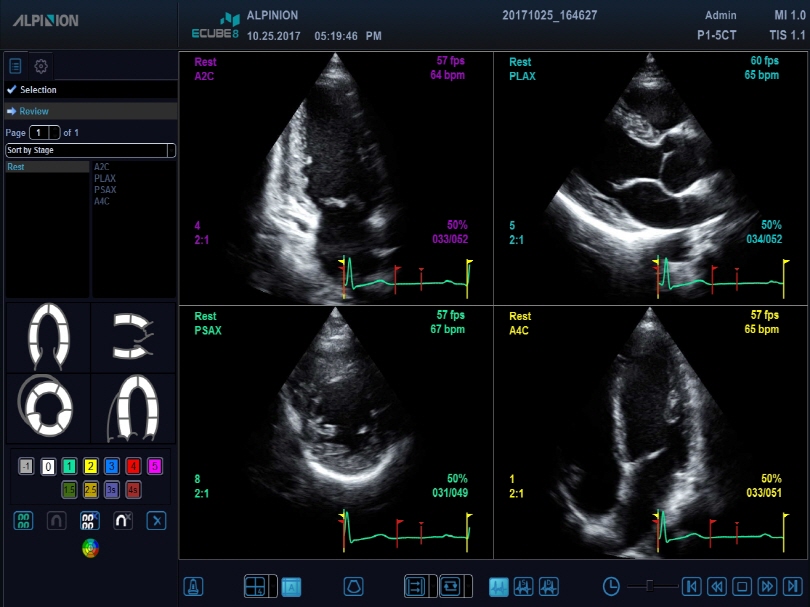

P1-5CT

Single crystal phased array transducer (1-5MHz)

Application:

Abdomen, Cardiac, EM, TCD